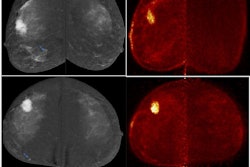

Dr. Yasmin Nada from the Baheya Foundation for Early Detection & Treatment of Breast Cancer in Egypt presents her team's findings at ECR 2023, showing that positron emission mammography (PEM) can successfully evaluate the response of breast cancer to neoadjuvant chemotherapy. Here, PEM shows breast tumors before and after chemotherapy in a 64-year-old woman. PEM showed complete response in this case.For this study, Nada and colleagues wanted to explore PEM's efficacy in monitoring neoadjuvant chemotherapy, as well as predicting residual disease in breast cancer. They tested their method on 38 breast cancer patients scheduled for chemotherapy. All patients underwent two PEM exams, one before and one after chemotherapy.

In another case, a 64-year-old woman with pathologically proven cancer of the left breast presented with multifocal outer-quadrant lesions. PEM performed after chemotherapy showed no FDG uptake, indicating complete response.